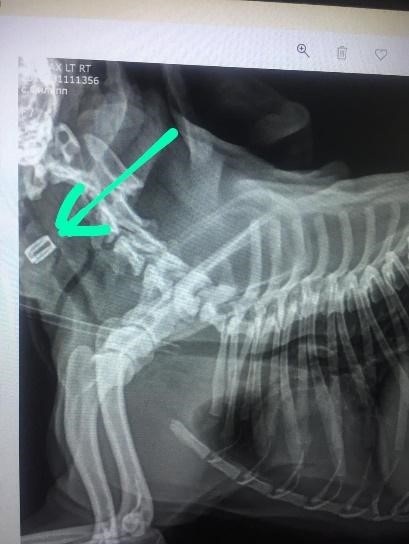

Рисунок 1. Результаты клинических испытаний: а) модель имплантата; б) имплантат в гортани мопса непосредственно после установки; в) интеграция имплантата через 9 дней после операции; г) рентгеновский снимок пациента, стрелка указывает на имплантата